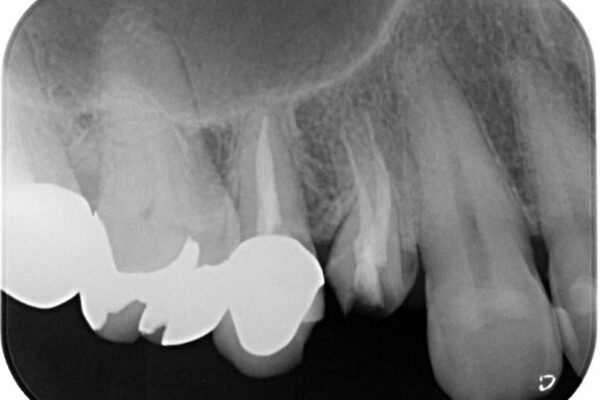

• 自然な美しさと強度を両立!右上小臼歯の被せもの脱離に対する審美補綴治療 治療前画像